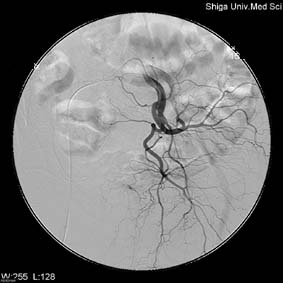

足の付け根や手首の血管などから、カテーテル(樹脂でできた直径1-2mmの長い管)を目的の血管まで挿入して造影剤を注入し血管の走行や状態を見る検査です。その時にそのカテーテルを利用して、狭くなった血管を広げたり、腫瘍の血管を詰めたり、また体内の出血を止めるなどの治療にも応用されています。(

Interventional Radiology : IVR )